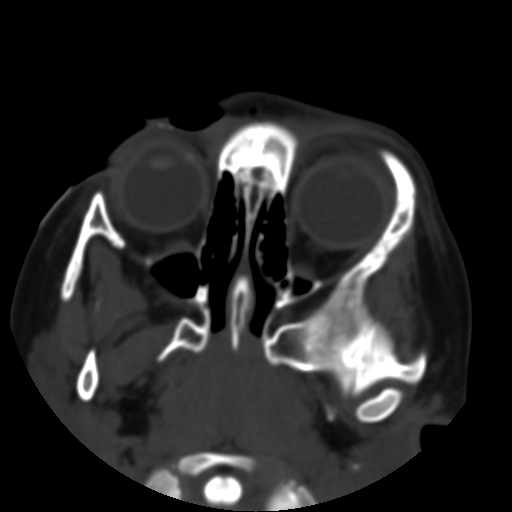

以下是引用深泽交通医院在2009-10-16 8:25:00的发言:[br]右眼环出血伴异物

以下是引用卜一在2009-10-16 15:01:00的发言:[br]右眼球挫裂伤伴异物!

以下是引用拾荒者在2009-10-17 18:38:00的发言:[br]鼻面部皮下积气,右侧睑缘及眼球壁高密度异物影,左侧眼球壁晶状体内侧缘处是圆形低密度影。低密度异物?应提请眼科医生注意。